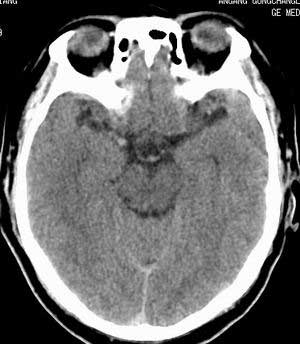

增强扫描:

平扫右侧岩骨与枕骨交角内侧脑质内见淡片状密度增高影,内缘清晰。增强图象上未见明显显示。

增强的横窦乙状窦。